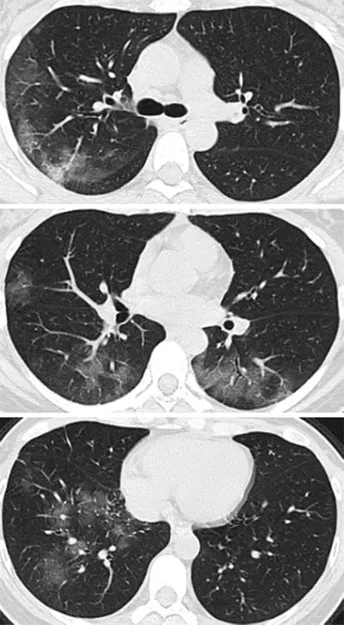

病例2,41岁女性,去了一趟武汉,

回来后,开始发热咳嗽,

4天后,她感觉呼吸困难,

去医院X线胸部拍片,检验血液,

都没有发现有啥异常。

但是CT扫描发现

两侧肺周边出现多处斑片状毛玻璃样显影。

01-3.webp

图片来自《Radiology》杂志